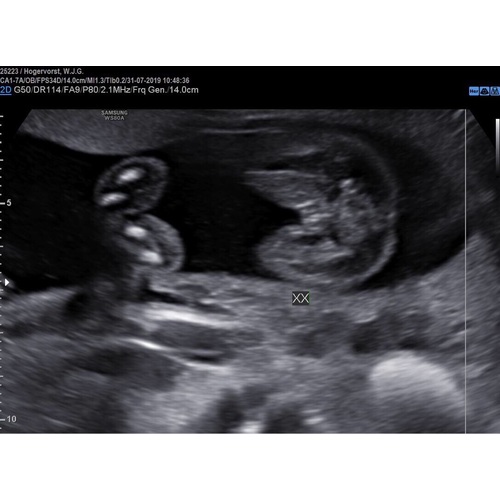

Ik heb nog even contact met haar gehad en ze stuurde me ook de nub nog toe en het beeld in 3d wel mogen we de 12e nog eens terug omdat ze toe gaf zelf ook te hebben getwijfeld en bang is dat onze twijfels daar door komen.. al ben ik aan de hand van de nub en het 3d beeld echt zeker dat het een meisje is toch fijn dat we even extra mogen kijken

Echo met 14 weken, jongetje ( al ben ik zelf nog wat sceptisch omdat het zo vroeg was ) 🙈